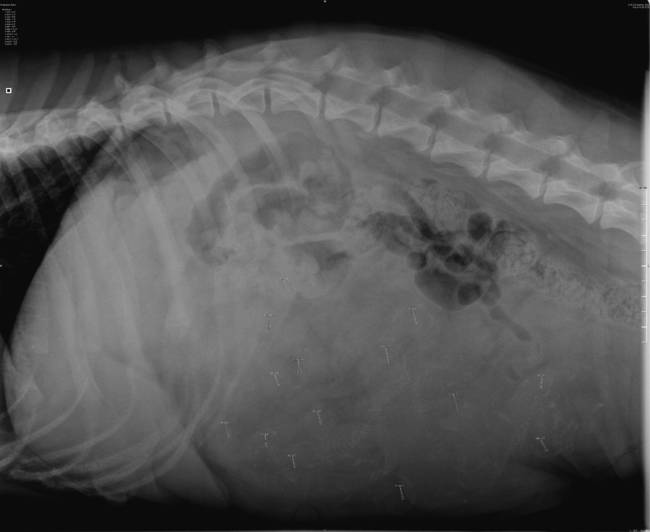

vraagje aan de fokkers onder ons of aan die gene die heel goed rontgen kunnen bekijken dit is een rx gemaakt op de 49 ste dag ven de dracht bij een bordeauxdog ik kan 14 pups tellen maar vind de foto onduidelijk

ik heb het geplaatst omdat ik een werkstuk moet maken ik ben bezig met een opleiding voor dierenarts assistente en er is mijn gevraagd om deze foto te bekijken en te oordelen omdat het dus steeds vaker voor komt dat de rx te onduidelijk zijn deze teef dracht ook veel vruchtwater bij zich ik hoop zo dat ik de informatie goed heb neergezet.gr cornelia

het is heel slecht te zien maar als je de foto vergroot zie je het iets beter maar dan nog moet je heel goed kijken.